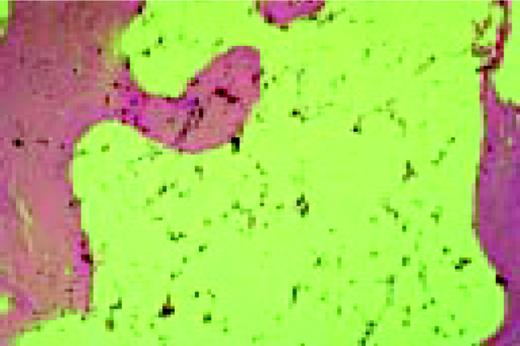

Agnogenic myeloid metaplasia with myelofibrosis. This low-power bone marrow biopsy clearly shows the fibrosis associated with this disease. This H&E-stained preparation shows virtual replacement of the marrow cavity with light pink-staining fibrotic tissue.FIG104

Slide E9